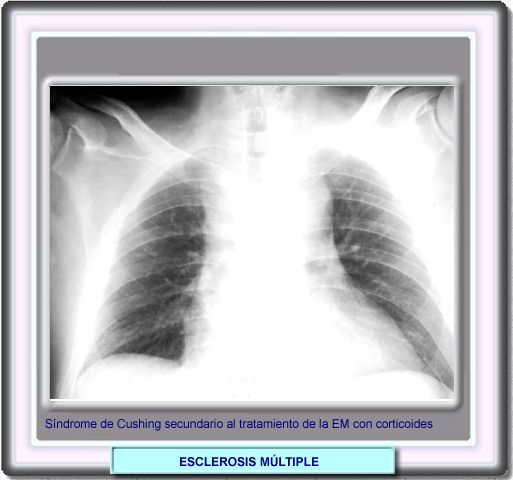

Los fármacos más utilizados en el tratamiento de la esclerosis múltiple (interferones y glatirámero) suelen ser bastante bien tolerados y presentan reacciones adversas ligeras. Por el contrario, los corticoides, que se utilizan frecuentemente para tratar los brotes agudos, pueden presentar serios efectos adversos, como este síndrome de Cushing en un paciente tratado con prednisona